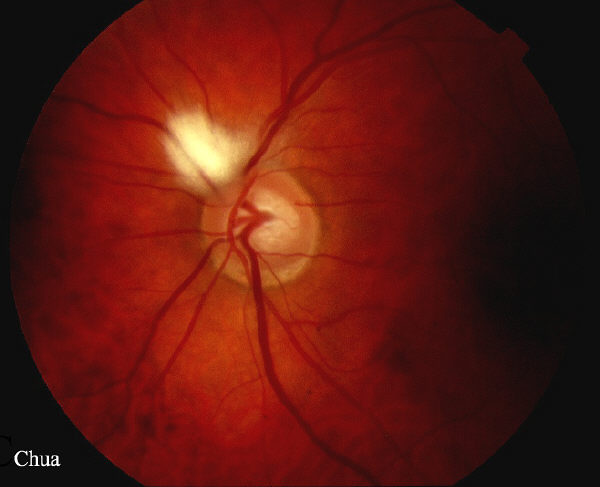

| History: An incidental finding of a patient with

bilateral myelinated nerve fibres. The myelination appears

white with feathery edges. Normally, myelination of the optic nerve stops at lamina cribosa but in some normal people it can extend onto the retina. Myelination if present often occurs around the optic disc but may be found anywhere on the retina. Visual fields in this patient will be expected to show increased blind spots as the myelination prevents light falling on the photoreceptors. |